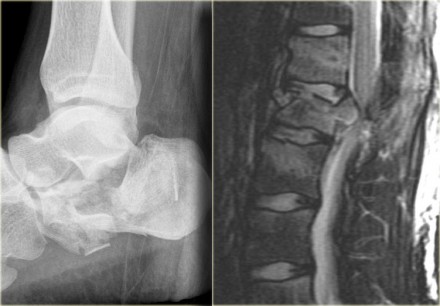

On the left a fracture of the calcaneus and a lumbar spine fracture.

This is called a 'jumpers fracture' or a 'lover's fracture', because it is usely seen in people jumping out of a window to escape from the police or a jealous husband.

In this case it is clear that we are looking at an unstable fracture, because this is a burst fracture.

Both the anterior and the middle column are disrupted.

In addition there is edema in the posterior soft tissues indicating that there is also involvement of the posterior column.

Notice also the marrow edema in the adjacent bodies due to the severe axial loading.